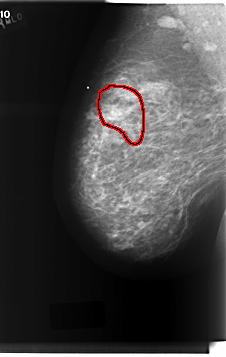

C_0213_1.RIGHT_MLO

RIGHT_MLO LINES 6056 PIXELS_PER_LINE 3840 BITS_PER_PIXEL 12 RESOLUTION 50 OVERLAY

FILE: C_0213_1.RIGHT_MLO.OVERLAY

TOTAL_ABNORMALITIES 1

ABNORMALITY 1

LESION_TYPE CALCIFICATION TYPE PLEOMORPHIC DISTRIBUTION SEGMENTAL

ASSESSMENT 5

SUBTLETY 5

PATHOLOGY MALIGNANT

TOTAL_OUTLINES 1

BOUNDARY